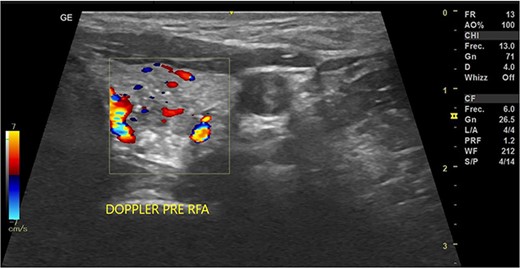

In May 2022, a thyroid ultrasound revealed a solid isoechoic left lobe TN measuring 12 × 11 × 13 mm, characterized by microcalcifications and irregular borders (Fig. 1). The color-flow Doppler ultrasound indicated increased perfusion, leading to its classification as a TI-RADS 5 nodule (Fig. 2). Elastography yielded a value of 2.2 (Fig. 3). Fine-needle aspiration confirmed Bethesda VI, consistent with thyroid papillary carcinoma.

Doppler thyroid ultrasound: transversal view, left lobe nodule doppler. Pre-RFA procedure.